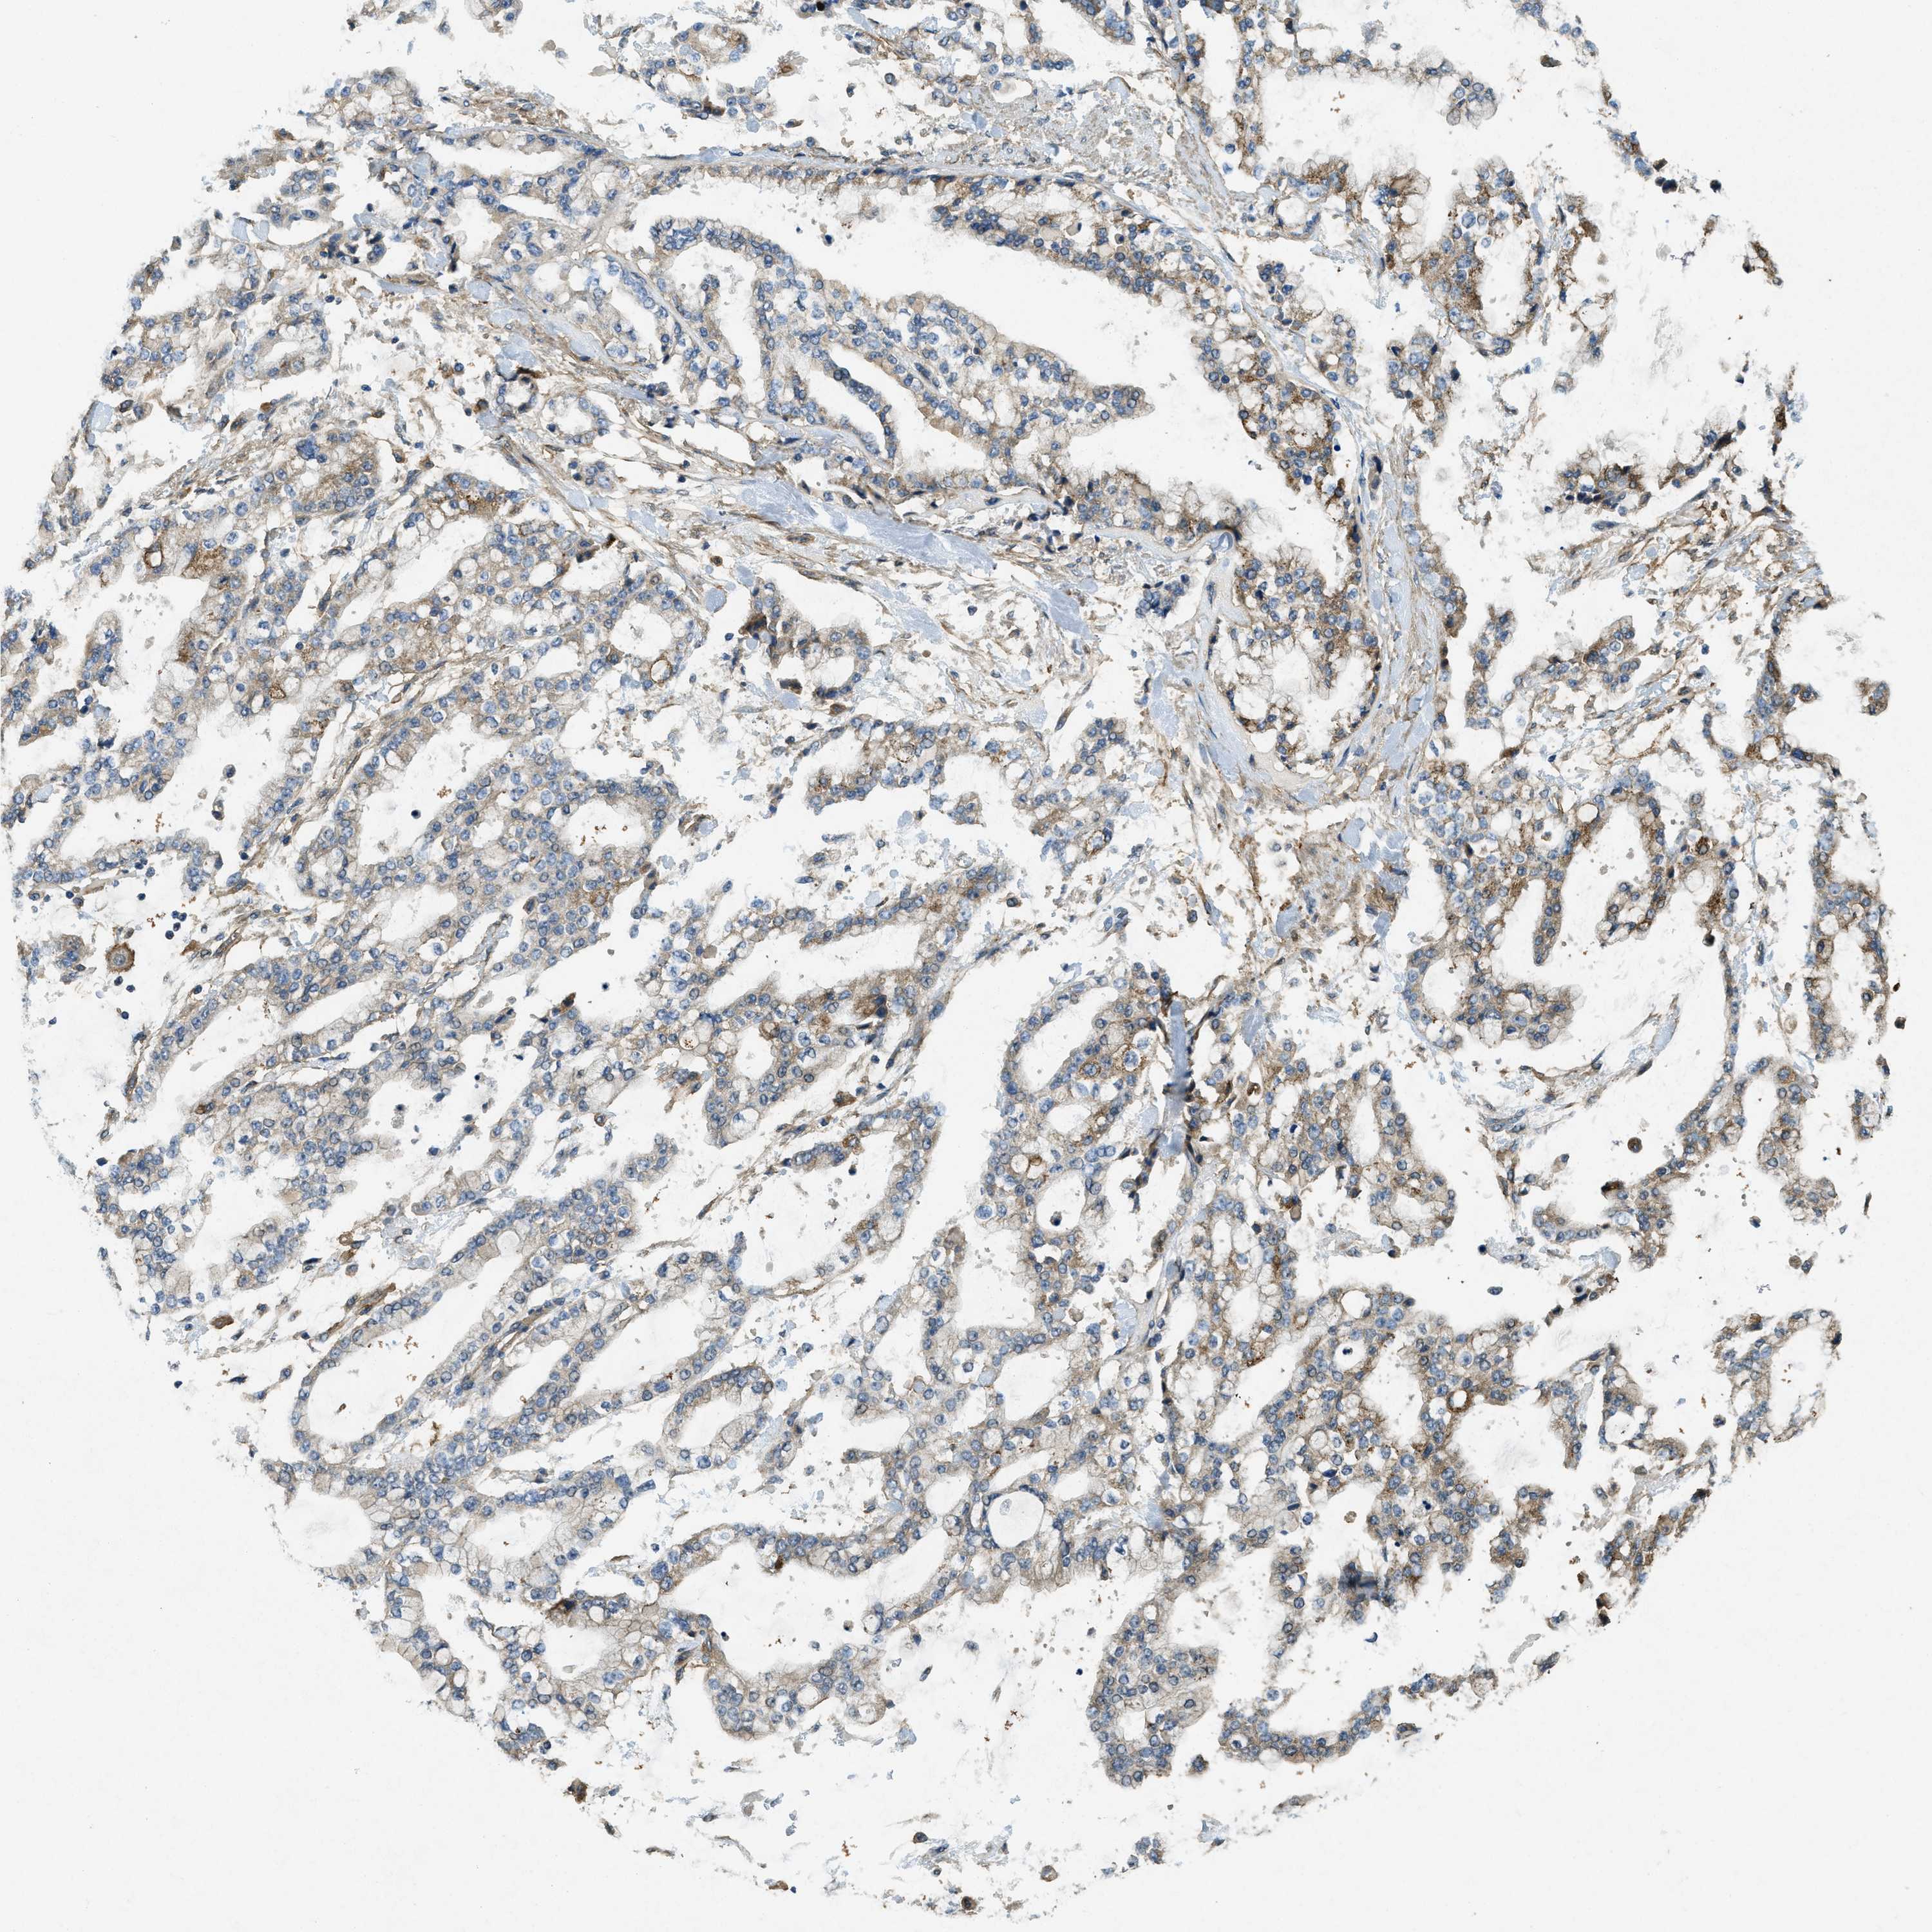

STOMACH CANCER - Protein expressioni

A mouse-over function shows sample information and annotation data. Click on an image to view it in a full screen mode. Samples can be filtered based on level of antibody staining by selecting one or several of the following categories: high, medium, low and not detected. The assay and annotation is described here.

Antibody stainingi

Antibody staining in the annotated cell types in the current human tissue is reported as not detected, low, medium, or high, based on conventional immunohistochemistry profiling in selected tissues. This score is based on the combination of the staining intensity and fraction of stained cells.

Each image is clickable and will lead to virtual microscopy that enables deeper exploration of all samples and also displays staining intensity scores, fraction scores and subcellular localization as well as patient and tissue information for each sample.

Antibody HPA009285

Antibody HPA017139

Antibody CAB017826

Staining

High

Medium

Low

Not detected

Intensity

Strong

Moderate

Weak

Negative

Quantity

>75%

75%-25%

<25%

None

Location

Nuclear

Cytoplasmic/membranous

Cytoplasmic/membranous,nuclear

Adenocarcinoma, NOS

Adenocarcinoma, High grade